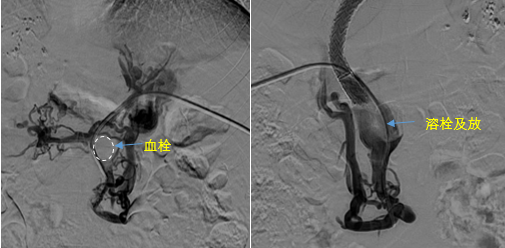

在西安國際醫(yī)學(xué)中心醫(yī)院,韓國宏教授對(duì)李女士進(jìn)行了細(xì)致的問診及檢查,在CT圖像上仔細(xì)的分析,針對(duì)患者特殊的病情制定了詳細(xì)的治療方案。第一次進(jìn)入手術(shù)室,在DSA的監(jiān)測(cè)下,造影過程中門靜脈血栓的輪廓逐漸顯現(xiàn)出來,見多識(shí)廣的醫(yī)生們也大吃一驚,發(fā)現(xiàn)遠(yuǎn)端脾靜脈及腸系膜上靜脈也存在大量血栓?;颊叩氖彻芪傅嘴o脈曲張非常嚴(yán)重,疏通堵塞的門靜脈已是刻不容緩。

見此情形,韓國宏教授憑借豐富的臨床經(jīng)驗(yàn)很快調(diào)整了策略,在超聲診療中心的協(xié)助下進(jìn)行門靜脈右支穿刺,并進(jìn)行造影,看到目標(biāo)血管后,韓國宏教授用“明修棧道,暗渡陳倉”的方法,讓來自脾臟和胃腸的血流終于暢通的回流到了肝靜脈。通過血流的沖刷以及抗凝溶栓藥物的作用,幾日后復(fù)查造影發(fā)現(xiàn)門靜脈血栓已逐漸變小,不會(huì)對(duì)回流到肝臟的血流產(chǎn)生大的阻礙作用,門靜脈的壓力顯著減小,患者再次出血的幾率也隨之降低。幾經(jīng)周折,這顆“定時(shí)炸彈”終于被拆除,李女士和她的家人多年來心里的石頭也終于落地。